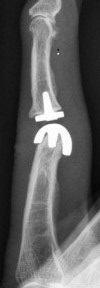

Aufsicht Röntgenaufnahme mit Abbildung eines | Röntgenaufnahme des selben Fingers nach Implantation einer Pyrro-Carbon Endoprothese | ||

Das "modernste" Implantat zum Ersatz des Fingermittelgelenkes wurde in einer Kombination aus teilbeschichtetem Edelstahl und Polyethylen, ähnlich dem Gelenkersatz am Kniegelenk, konstruiert. Erste Ergebisse sind sehr vielversprechend, doch fehlen leider noch Langzeitergenisse | Ein weiterer Vorteil dieses "Designs" ist der geringe Knochenverlust bei der Implantation. Sollte es irgendwann zum Auslockern oder Funktionsverlust kommen ist ggf. eine Wechsel-Operation möglich. |